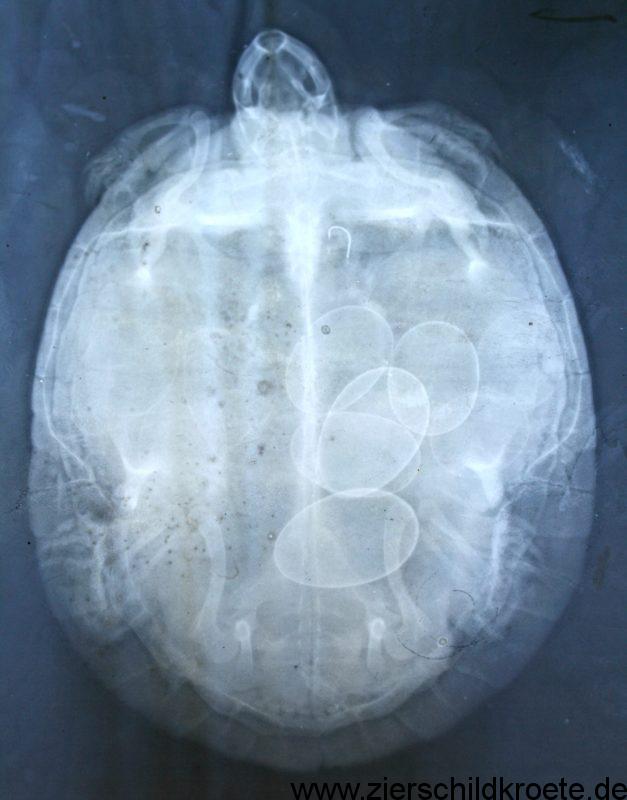

Die Symptome sind nicht sehr eindeutig, Klarheit bringt ein Röntgenbild, auf welchem man die Eier erkennen kann. Die Wasserschildkröte wirkt meist sehr unruhig und läuft tagelang auf der Suche nach einer Eiablagestelle auf dem Landteil herum.

Ein Reptilienarzt wird als wehentreibendes Mittel Oxitocin verabreichen. Wird dieses Hormon verabreicht bekommt die Schildkröte starke Wehen und treibt die Eier aus, egal wo sie gerade ist. Um eine schnelle Wirkung zu erzielen ist es sinnvoll sie dazu in ein warmes Wasserbad zu setzten. Diese Spritze darf nicht verabreicht werden ohne vorher über ein Röntgenbild abgeklärt zu haben ob eventuell Eier kaputt sind oder zu groß für das Becken. Es ist für die Schildkröte auch bei „normalen“ Eier eine große Belastung die Eier per Spritze abzulegen. Mir tun die Tierchen dabei sehr leid, es ist wirklich kein schöner Anblick wie sie die Eier dann ablegen. Die Eier routinemäßig per Hormoninjektion aus der Schildkröte zu holen anstatt einen Eiablageplatz anzubieten (und ihn so lange zu verbessern bis die Schildkröte ihn annimmt) ist in meine Augen übelste Tierquälerei. Die Oxytocin-Spritze ist also keine Prophylaxe einer Legenot, sondern eine Therapie im Notfall um das Leben der Schildkröte zu retten. Gibt es kaputte oder zu große Eier ist eine Operation unter Vollnarkose mit Aufsägen des Panzers nötig.